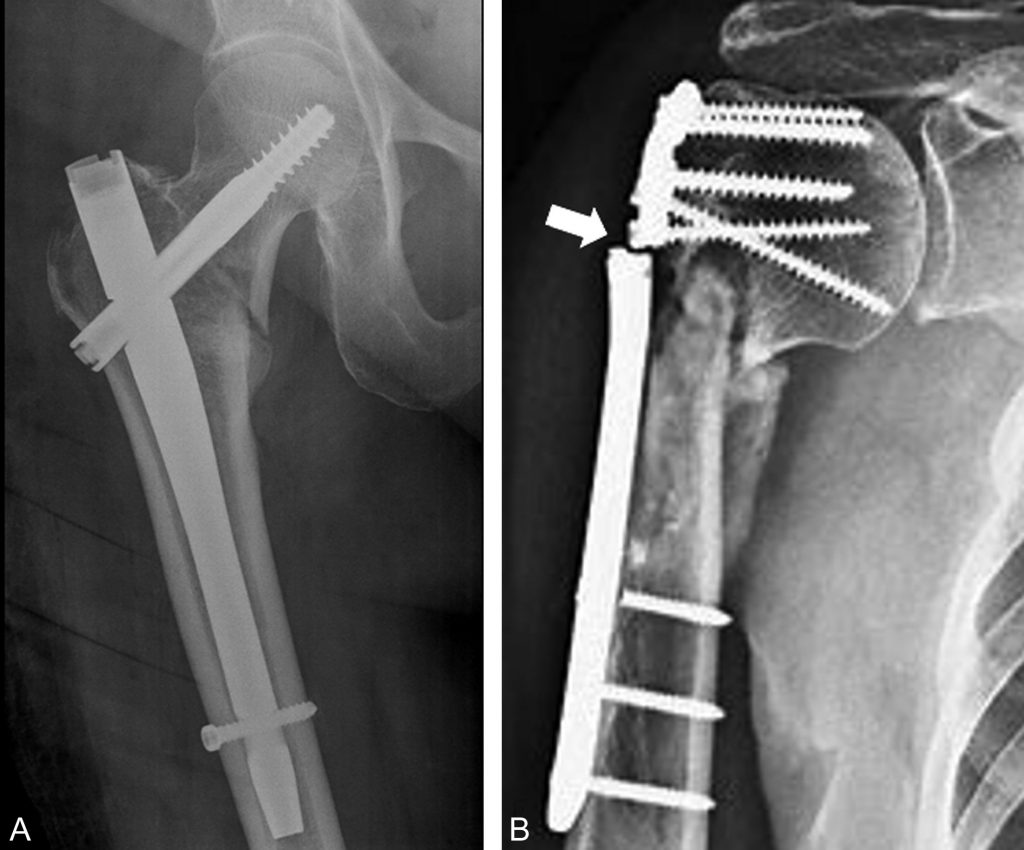

Fig. 82.2 Ostéosynthèses.

(A) Ostéosynthèse d’une fracture pertrochantérienne par un clou gamma. Radiographie de la hanche droite de face réalisée après intervention, sans signe de complication immédiate. (B) Pseudarthrose d’une fracture du col chirurgical de l’humérus droit avec fracture de la plaque vissée.

Source : CERF, CNEBMN, 2022.